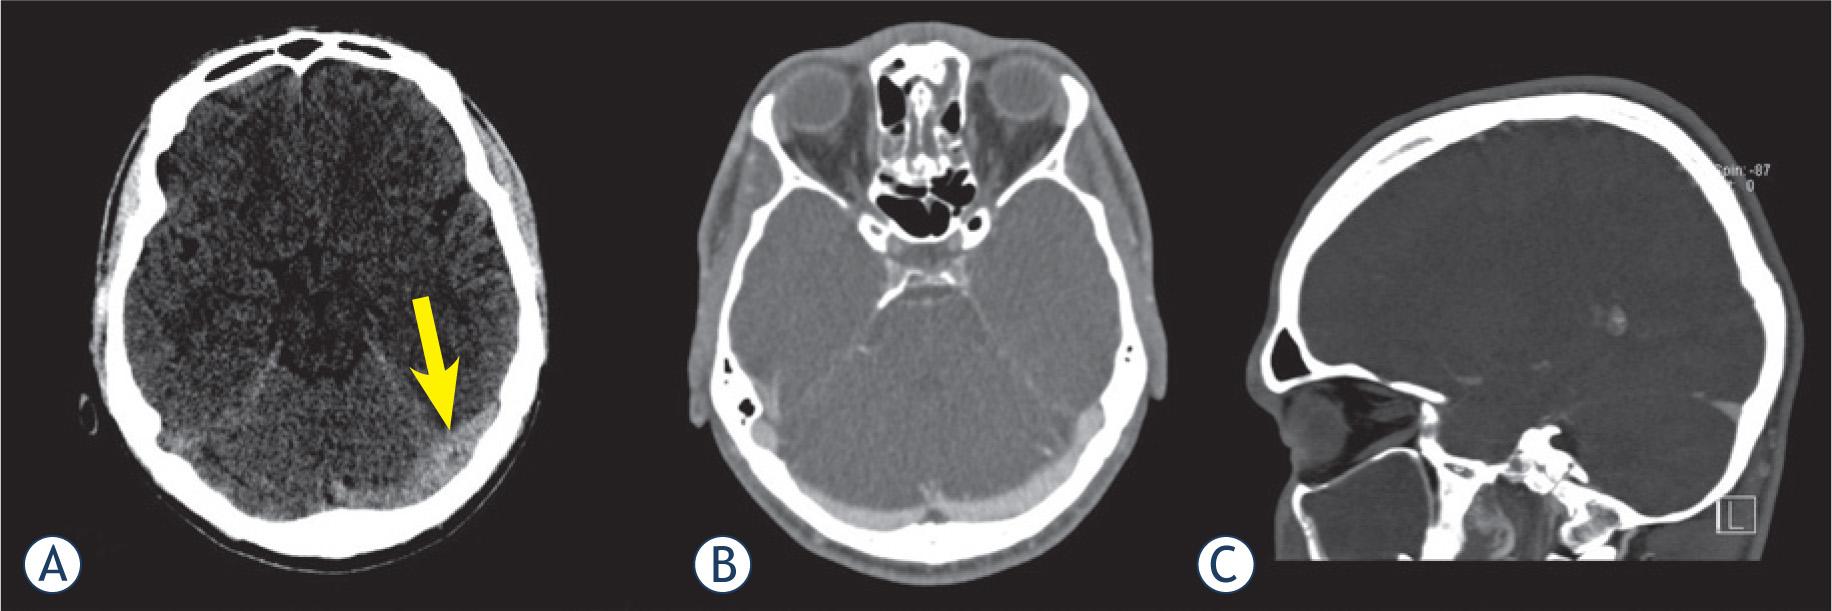

Transverse sinus was the most commonly thrombosed structure, followed by sigmoid sinus (Table 1). Typical NCCT findings of CVST are depicted in Figure 1. All 13 patients with CVST were accurately diagnosed by both observers. Therefore, the calculated sensitivity was 100% in both readings, with specificity of 80 and 87.5%, respectively. Kappa value regarding the presence or absence of thrombosis was 0.72, which is considered to represent a good agreement between observers. Sensitivity and specificity of NCCT for overall presence of thrombosis were 100% and 83%. Average diagnostic confidence level regarding the presence or absence of CVST was 2.1 ± 1.2 (very certain). A case with false positive finding is depicted in Figure 2.

Left transverse sinus (LTS) of a 26-year-old male appeared hyperattenuated on non-contrast computed tomography (arrow) (A) and was interpreted as thrombosed by both readers. However, CT venography in axial (B) and sagittal (C) reconstruction showed patency of the LTS. Average attenuation inside the LTS was 60 HU.